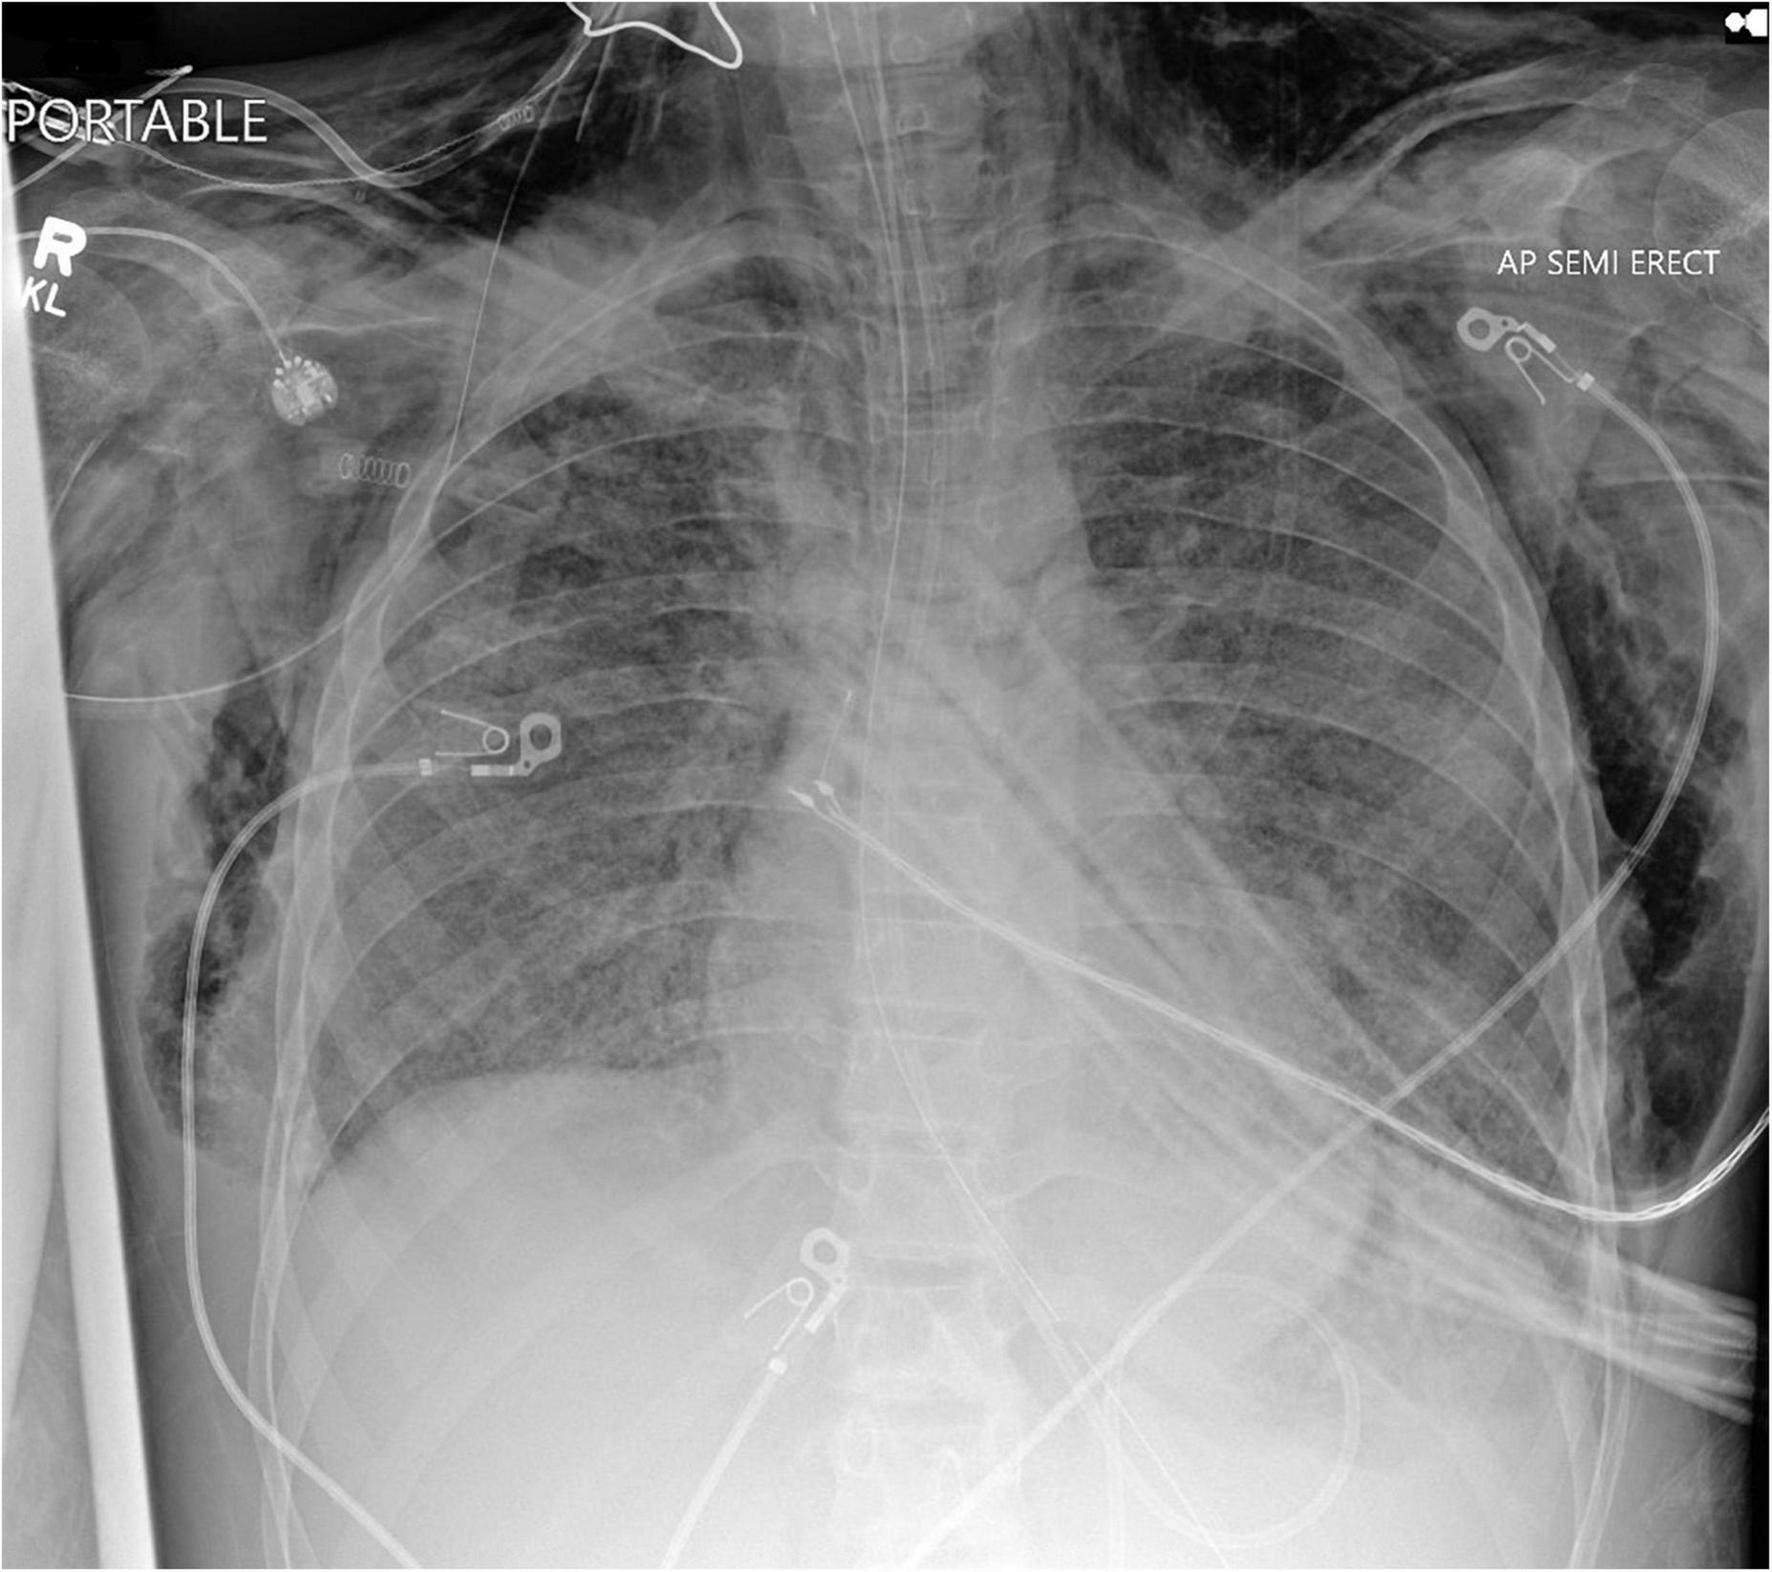

Aggressive mechanical ventilation and resulting barotrauma or volutrauma is the most frequent etiology of air leak syndromes such as pneumothorax, pneumomediastinum, and subcutaneous emphysema in the PICU. Mechanical ventilation of children with obstructive lung physiology can also result in hyperinflation secondary to inadequate expiratory flow and thereby lead to life threatening air leak. However, with the adoption of lung protective ventilation strategies in the pediatric population, the incidence of air leak syndromes in mechanically ventilated patients has decreased. Subcutaneous emphysema is rarely clinically significant, but can be cosmetically disconcerting for parents of pediatric patients. Management of subcutaneous emphysema is mainly conservative through limiting airway pressures and allowing time for resolution of air leak. Active treatment is rarely warranted or undertaken, but there are published reports on the use of “micro-drainage” through fenestrated subcutaneous catheters in the adult population (17–19). However, no such reports are available in the pediatric population. Figure 1 shows an anonymized patient with massive subcutaneous emphysema and pneumomediastinum without any hemodynamic instability.

FIGURE 1

Chest radiograph of a mechanically ventilated pediatric patient, demonstrating subcutaneous emphysema und pneumomediastinum, in the absence of hemodynamic compromise.